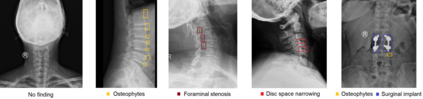

Radiographs are used as the most important imaging tool for identifying spine anomalies in clinical practice. The evaluation of spinal bone lesions, however, is a challenging task for radiologists. This work aims at developing and evaluating a deep learning-based framework, named VinDr-SpineXR, for the classification and localization of abnormalities from spine X-rays. First, we build a large dataset, comprising 10,468 spine X-ray images from 5,000 studies, each of which is manually annotated by an experienced radiologist with bounding boxes around abnormal findings in 13 categories. Using this dataset, we then train a deep learning classifier to determine whether a spine scan is abnormal and a detector to localize 7 crucial findings amongst the total 13. The VinDr-SpineXR is evaluated on a test set of 2,078 images from 1,000 studies, which is kept separate from the training set. It demonstrates an area under the receiver operating characteristic curve (AUROC) of 88.61% (95% CI 87.19%, 90.02%) for the image-level classification task and a mean average precision (mAP@0.5) of 33.56% for the lesion-level localization task. These results serve as a proof of concept and set a baseline for future research in this direction. To encourage advances, the dataset, codes, and trained deep learning models are made publicly available.